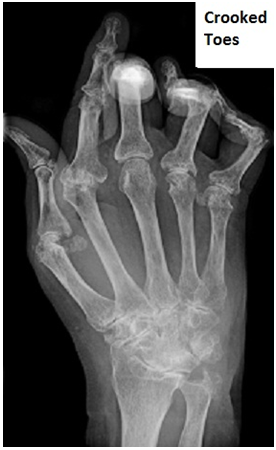

The structure of the toes is what enables humans to stand stably on their two feet. It is the combination of these five digits on each foot connected with a combination of muscles, tendons, and nerves that enables activities like walking, standing, and everything that requires the use of the foot. There are a number of conditions and diseases that may affect the toes. Crooked toes are one of the most common problems associated with this joint. There are different types of crooked toes, for example, mallet, overlapped, claw, and hammer toes. They might cause problems in functioning and can also be painful.

In the scenario of a claw toe, the toe forms a claw-like shape. It is often called a mixture of mallet toe and hammer toe. The ball joint is jutted upwards whereas the middle joint is bent downwards making the toe look like a claw. The toes literally dig into the ground while walking and hence corns and calluses are a common result of claw toes.